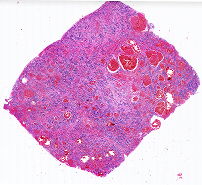

10516 |

左乳肿块 |

女, 66岁, 发现左乳无痛性肿块1月。

查体:双乳外观对称,发育正常,皮肤... |

上海市第六人民医院 |

有诊断 |